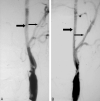

Background and purpose: Two large trials indicated that endarterectomy was less beneficial for symptomatic patients with internal carotid artery (ICA) near occlusion than for patients who had severe stenosis without near occlusion. Near occlusions complicate ratio calculations of ICA stenosis and require attention to detail for identification. The goal is to provide diagnostic criteria, illustrate identifying features, estimate accuracy of identification, and assess prognosis for patients with near occlusion.

Methods: We re-reviewed 1216 patients with severe (> or =70%) stenosis on angiography in the North American Symptomatic Carotid Endarterectomy Trial and European Carotid Surgery Trial. One of 5 (n = 262) had 2 or more criteria for near occlusion: (1) delayed cranial arrival of ICA contrast compared with external carotid artery (ECA); (2) intracranial collaterals seen as cross-filling of contralateral vessels or ipsilateral contrast dilution; (3) obvious diameter reduction of ICA compared with opposite ICA; or (4) ICA diameter reduction compared with ipsilateral ECA.

Results: Interrater agreement, sensitivity, and specificity were excellent (0.88, 90.6%, and 93.8%, respectively). By intention to treat, 3-year risks of ipsilateral stroke for medically treated patients with near occlusion was 15.1% versus 10.9% for surgically treated (absolute risk reduction [ARR] = 4.2%; P value = .33). Patients who continued to receive treatment in the medical arm for the trial's duration had a 3-year risk of 18.3% (ARR = 7.4%; P value = .13). Medically treated patients with severe stenosis but without near occlusion had a 3-year risk of 26.0% versus surgically treated of 8.2% (ARR = 17.8%; P value < .001).